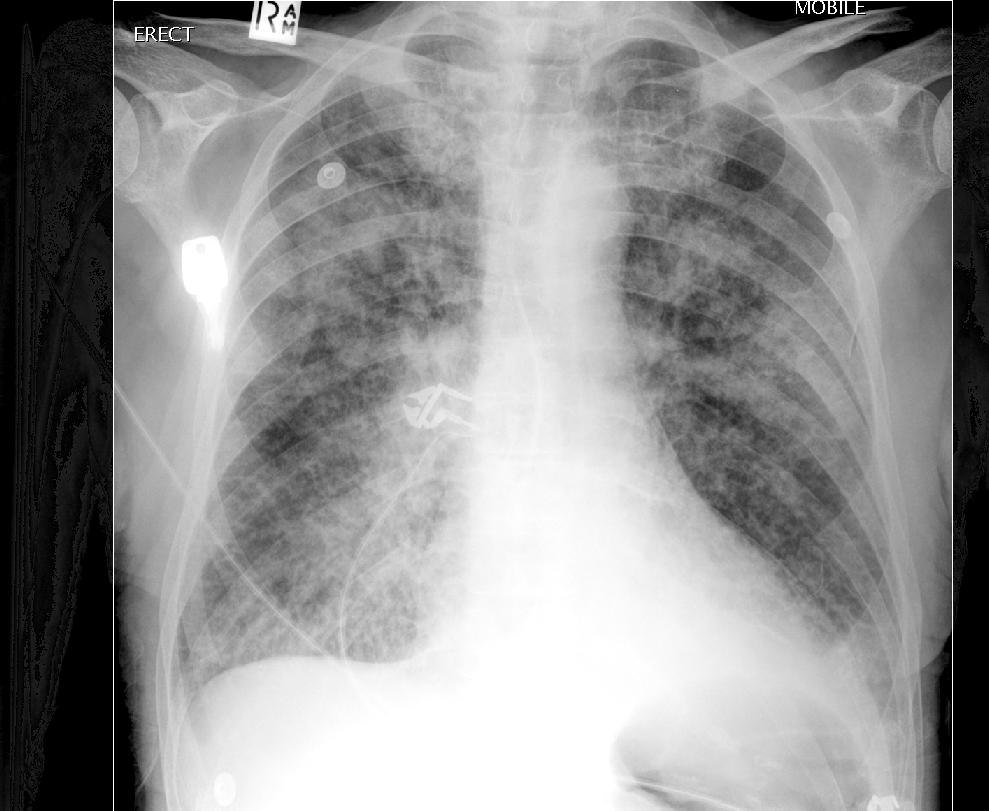

Рентгенограмма грудной клетки

Отек легких может быть обнаружен у взрослых людей на рентгенограмме грудной клетки, когда внесосудистая вода в легких (EVLW) увеличивается примерно на 35%. Хотя большинство рентгенографических признаков отека легких неспецифичны, улучшенные рентгенографические методы в сочетании с улучшенным пониманием патофизиологии отека легких повысили полезность рентгенограммы грудной клетки в диагностике отека легких.

Линии Керли представляют собой междольковые листы аномально утолщенной или расширенной соединительной ткани, которые касаются рентгеновского луча (рис. 36.4). Их более правильно назвать линиями перегородки. Утолщение перегородок может быть результатом различных процессов, включая фиброз, отложение пигмента и легочный гемосидероз. Однако, когда они временные, эти линии обычно вызваны отеком. Эти перегородки отека более отчетливо видны у детей старшего возраста и взрослых с хроническим отеком, чем у младенцев, предположительно потому, что они шире.

Периваскулярные и перибронхиальные манжеты также являются рентгенологическими признаками интерстициального отека жидкости. По гидростатическим причинам периваскулярный отек наиболее выражен в гравитационно-зависимых регионах, и поэтому нормальное связывающее действие легких в этой области меньше. Повышенное сопротивление сосудов нижних долей способствует перераспределению крови к верхним долям. Этот признак, конечно, имеет ограниченную ценность для младенцев, потому что они, скорее всего, находятся в положении лежа на спине, имеют меньшие гравитационные различия из-за своего размера и обычно имеют лишь немного повышенное давление в ПА по сравнению с детьми и взрослыми.

Более тяжелые формы отека легких обычно приводят к появлению перихилярного помутнения, предположительно потому, что в этом месте находятся большие периваскулярные и перибронхиальные скопления жидкости. Также может присутствовать ретикулярный или решетчатый узор, который чаще встречается внизу у вертикального человека.

Когда отек легких становится достаточно серьезным, чтобы привести к стойкому закрытию дыхательных путей или альвеолярному затоплению, очень трудно разделить отек, ателектаз и воспаление на рентгенограммах грудной клетки.Воздушные бронхограммы указывают на безвоздушные дистальные отделы легких, а не на первопричину.

Поскольку отек легких может привести к обструкции дыхательных путей у детей как из-за блуждающего рефлекса 27 , так и из-за бронхиальной пены, может произойти закрытие дыхательных путей 32 и образование воздушных ловушек. 29 Таким образом, низкая диафрагма может быть полезным признаком интерстициального отека при отсутствии других причин обструкции дыхательных путей. Хотя исследования у детей ограничены, обобщение результатов, позволяющих разделить кардиогенный или гемодинамический отек, почечный или гипергидратационный отек и травму или отек с ОРДС, было предоставлено у взрослых. 33,34 У пациентов с сердечной недостаточностью наблюдается обратное перераспределение кровотока от основания к верхушке.

Постепенное пополнение соединительнотканных пространств отечной жидкостью как при сердечных, так и при почечных заболеваниях приводит к размытости корней, перибронхиальным наручникам и нечеткой картине увеличения плотности легких. При ОРДС более вероятно неоднородное периферическое распространение отека и небольшое количество таких признаков, как перегородки и перибронхиальные манжеты.